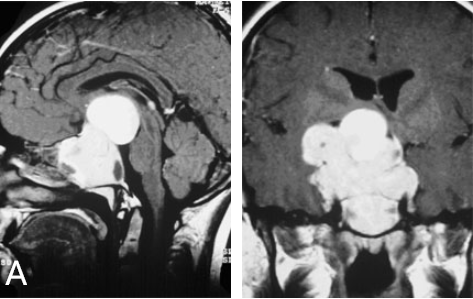

垂体瘤是一组从垂体前叶和后叶及颅咽管上皮残余细胞发生的肿瘤,约占颅内肿瘤的10%,以前叶的腺瘤占大多数,来自后叶者少见。垂体瘤大部分为良性腺瘤,极少数为癌,好发年龄为青壮年,发病率为1/10万。